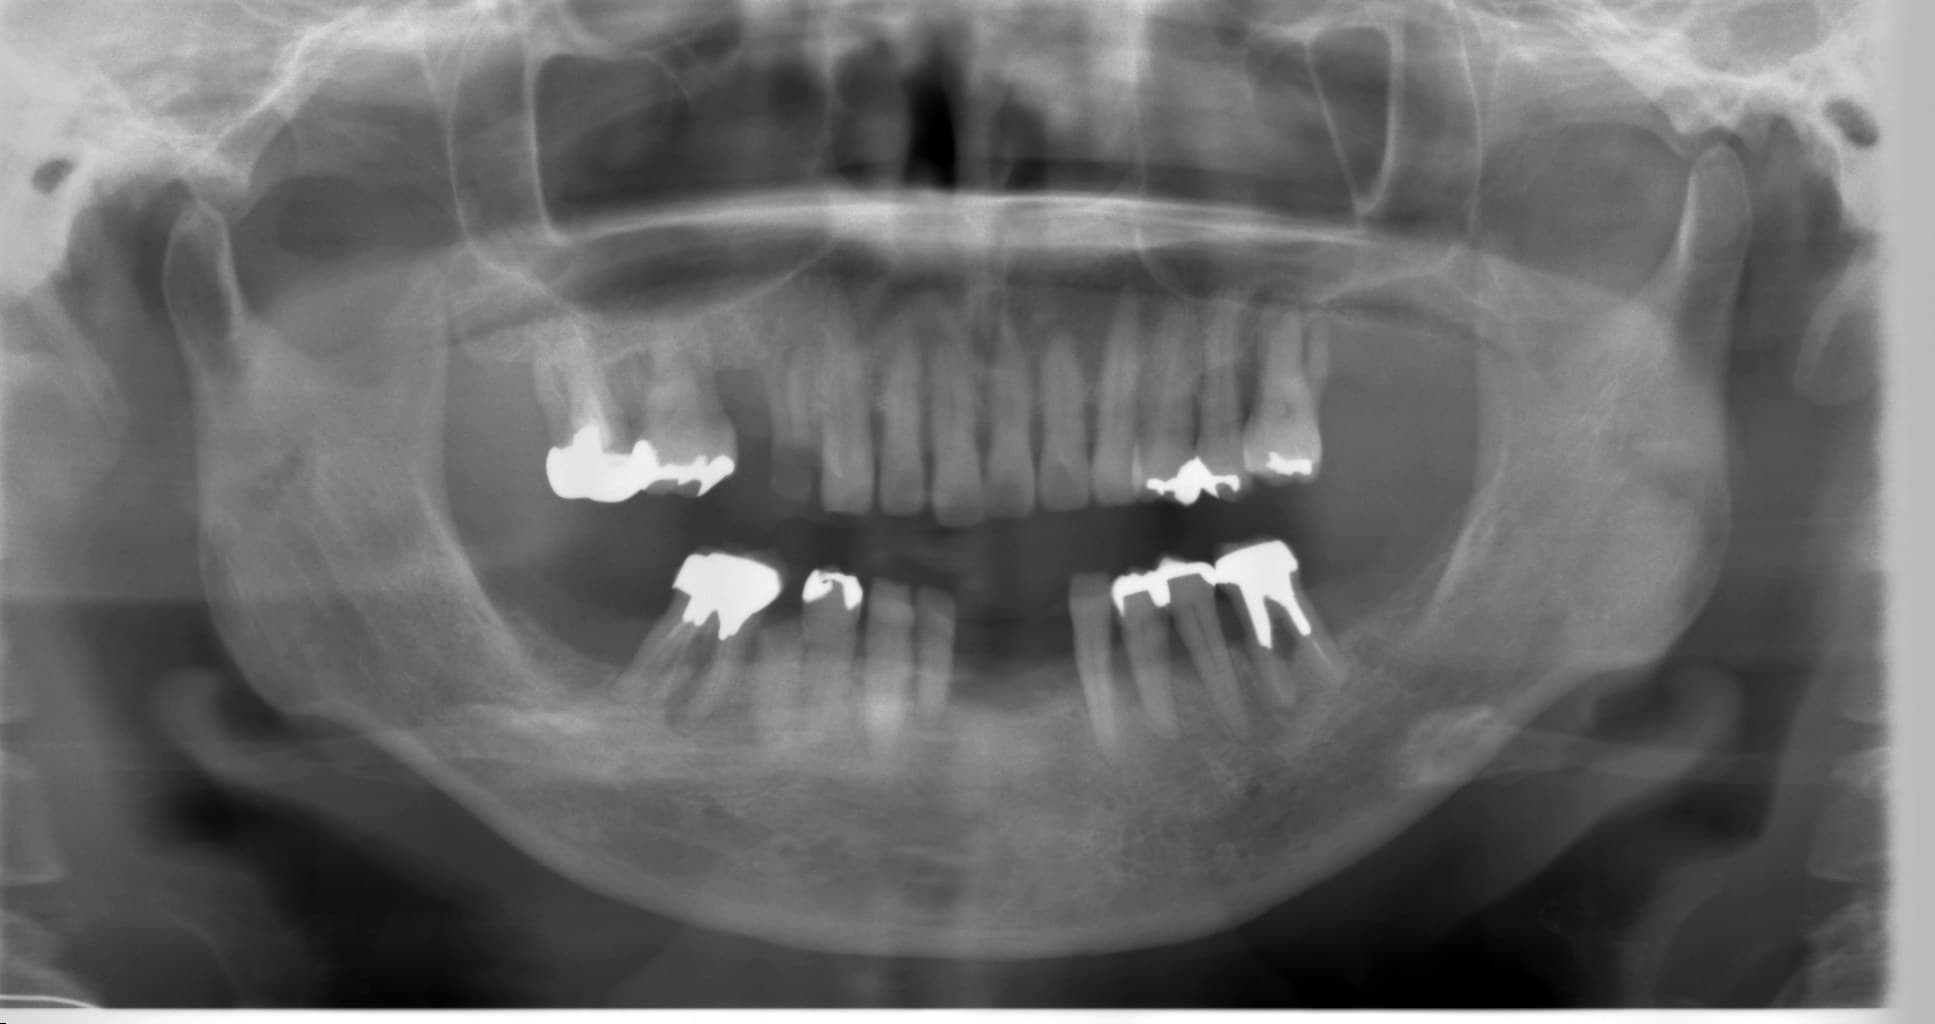

歯周病治療を行った症例をご紹介します。

50代の女性の方です。

以前から歯がぐらついてきて、そのたびに歯医者に通い歯を抜いていたそうです。

治療に行く度に抜歯をする中で、「どうしても、自分の歯で生活をしたい」という思いが芽生え、来院してくださいました。

重度の歯周病で、出血があり歯もグラグラして、歯周ポケットは5~8mmと深くありました。

初診時から3年経った現在も、グラグラや出血は落ち着き、大変おきれいにセルフケアを続けて頂いています。